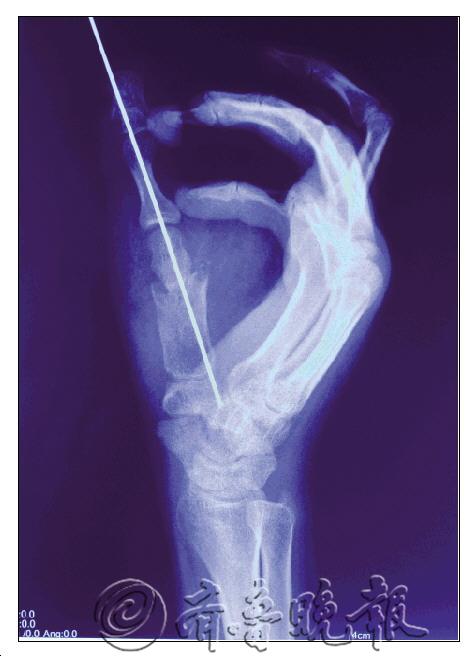

近年来,骨科医院在“大专科”方面取得了较快发展。众所周知,我国在手外科领域一直处于世界领先地位,而据孙院长介绍,骨科医院目前在相关领域,特别是手指再造技术已经是处于国内领先水平。“手足显微外科以精湛的技术和雄厚的竞争实力,熟练开展了小儿断指再植、多指断指再植和一指多断断指再植等不同类型的高难度断指(肢)再植手术,成活率达90%;拇、手指再造手术的成活100%。拿断指再植手术为例,原来需要十多个小时才能完成,现在只需三小时左右。”孙院长说,除此之外,骨科医院在复杂手外伤处理及功能重建、小儿手足先天畸形矫形、肌肉肌腱转位修复肢体功能障碍等方面也属国内领先技术。

科室熟练开展小儿断指再植、多指断指再植和一指多段断指再植等不同类型的高难度断指(肢)再植手术,成活率98.5%;拇、手指全形再造手术,成活率100%;成功开展复杂手外伤处理及术后功能重建、小儿手足先天畸形矫形手术、臂丛神经及周围神经损伤诊断治疗、肌肉肌腱转位修复肢体功能障碍等手术;熟练掌握髓内钉、锁定钢板、四肢异性钢板、掌指骨微型钢板、动力髋、髁等新型内固定技术。四肢皮肤软组织缺损的各种带蒂及游离皮瓣修复、手部皮肤软组织缺损的各种微型皮瓣修复、股骨头无菌坏死等技术在国内领先。